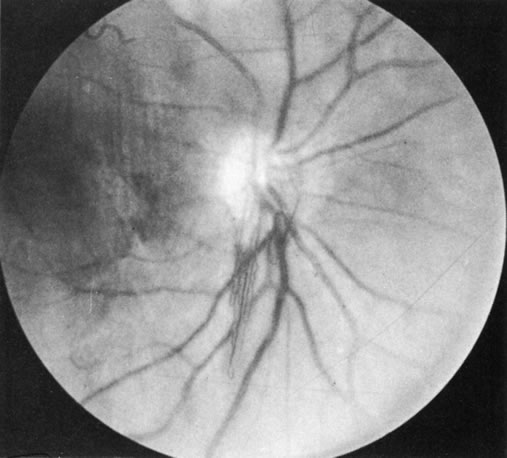

Behçet's disease is a chronic inflammatory disease with widespread clinical manifestations. It affects adults of both sexes, especially in Mediterranean countries and Japan. Classically it consists of a triad of recurrent lesions: iritis, oral ulcers, and genital ulcers (Fig. 6).34 Other common features are vasculitis, skin lesions, optic papillitis (Fig. 7), arthritis, meningomyelitis, and inflammatory bowel disease. Loss of vision is one of its most frequent and serious manifestations. In Japan, the disease is said to be responsible for one-third of all cases of uveitis. Ocular disease occurs in 75% of affected patients, usually in the form of hypopyon, uveitis, occlusive retinal vasculitis, and optic nerve lesions. The cause of Behçet's disease is unknown, but viral, immunologic, and hereditary factors have been suspected.

Fig. 6. Hypopyon iritis in Behçet's disease. (Courtesy of Dr. K. Yamaguchi.)

Fig. 7. Optic papillitis in Behçet's disease. (Courtesy of Dr. G. Mintsioulis.)